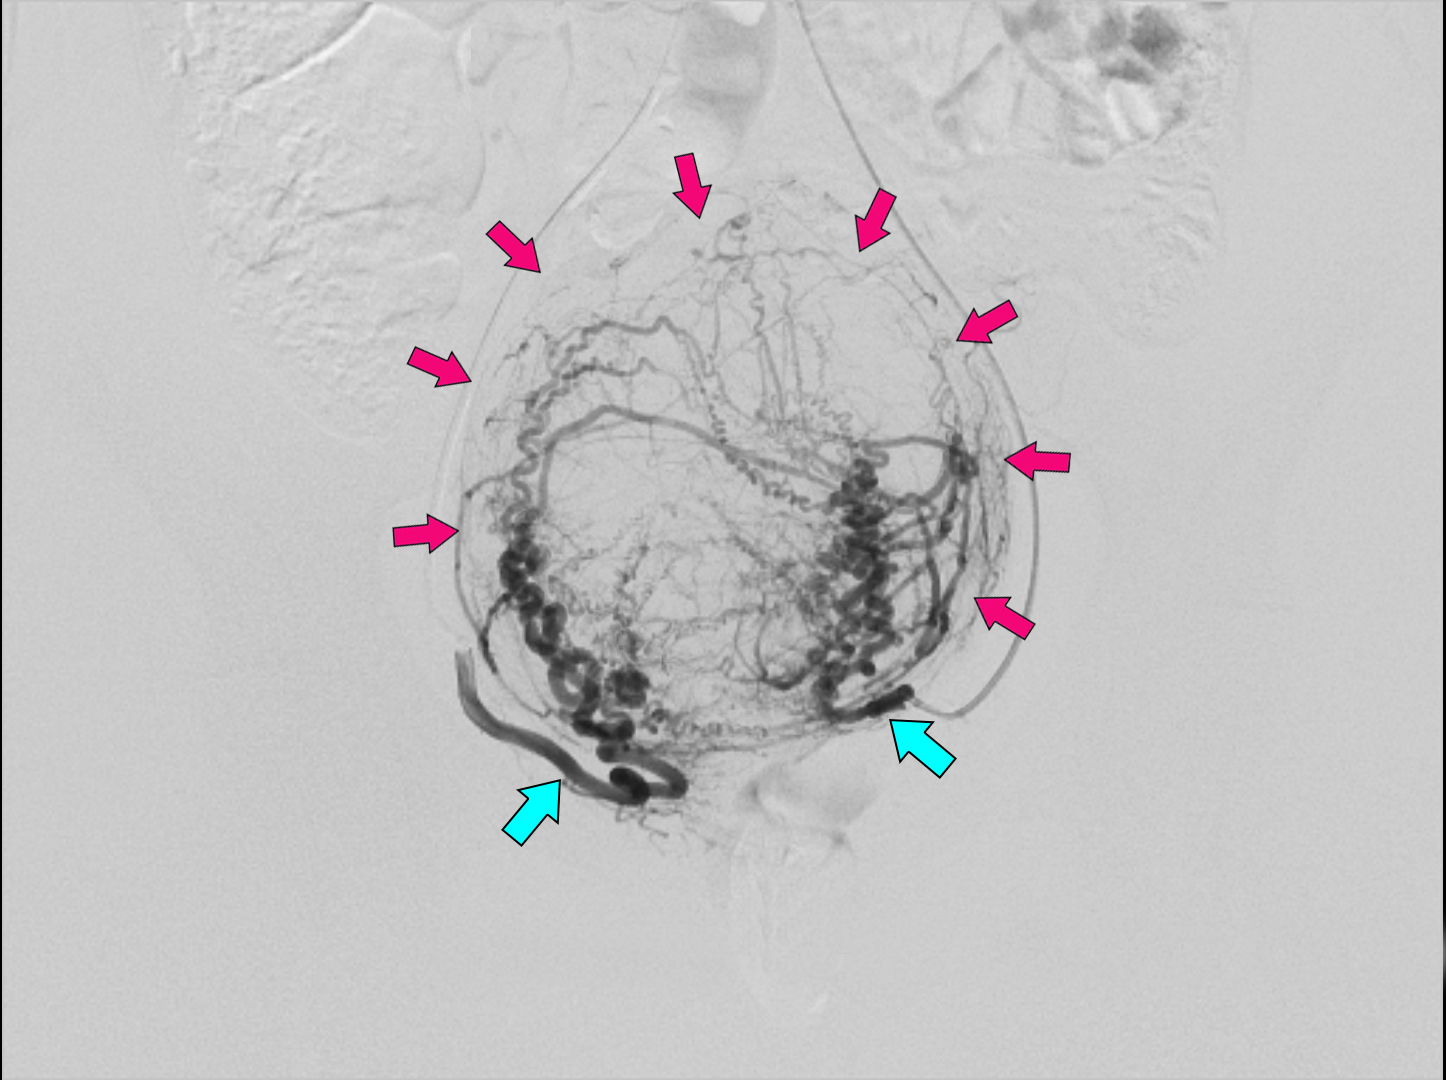

До/Після виконання втручання

Блакитними стрілочками позначено праву та ліву маткові артерії

Малиновими стрілочками позначено обриси фіброміоми які сформовані судинним малюнком